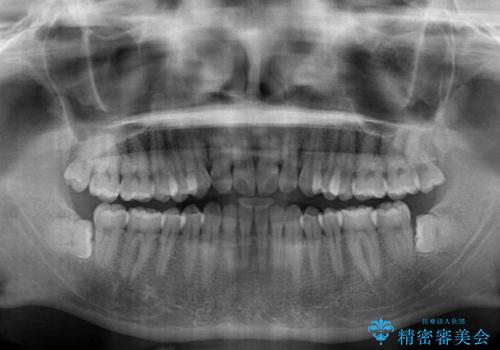

下顎前歯と上顎の部分矯正

- 上下の前歯の叢生を気にして来院された患者様です。

前歯のみの矯正治療を希望でしたが、上顎臼歯が舌側転位していたため、上顎は全体を、下顎は前歯のみを矯正治療することとしました。